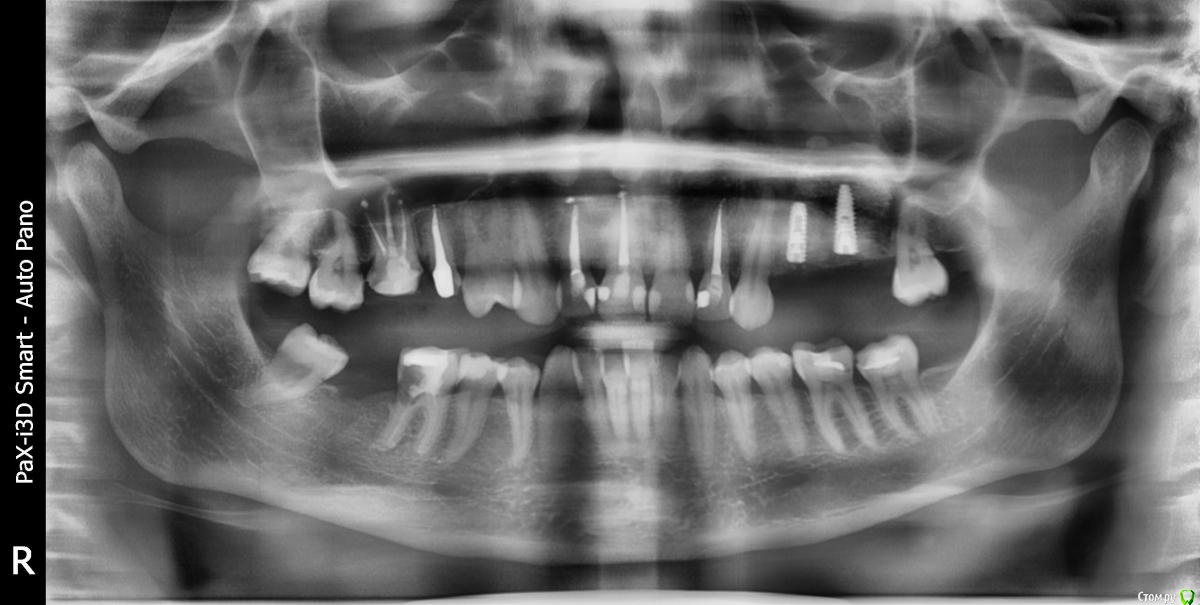

kamranchick Опубликовано 4 мая, 2018 Поделиться Опубликовано 4 мая, 2018 Добрый день Уважаемые коллеги, имеются проблемы с ортодонтией в нашем славном городе.Какие будут предложения по кейсу, сколько визитов и по ценникам, можно в личку.Пациент готов ездить в другие городаP.S пациент тоже будет следить за ходом этой ветки))) Ссылка на комментарий

krokomot Опубликовано 4 мая, 2018 Поделиться Опубликовано 4 мая, 2018 А импланты уже успели установить. 1 Ссылка на комментарий

kamranchick Опубликовано 4 мая, 2018 Автор Поделиться Опубликовано 4 мая, 2018 А импланты уже успели установить.Как видите вопросов много конечно, но что можно предложить имея такую картину. Ссылка на комментарий

krokomot Опубликовано 4 мая, 2018 Поделиться Опубликовано 4 мая, 2018 а снижение высоты есть? Ссылка на комментарий

kamranchick Опубликовано 4 мая, 2018 Автор Поделиться Опубликовано 4 мая, 2018 а снижение высоты есть?Ну углы рта опущены, модели не видел Ссылка на комментарий

krokomot Опубликовано 4 мая, 2018 Поделиться Опубликовано 4 мая, 2018 в данной ситуации конечно шляпа у пациента, если совсем все плохо, можно бы, ло бы просанировать для начала, снять скан, затем, поробовать на инвизилайнерах решить основные проблемы в окклюзии , затем тотальное протезирование. Идейка конечно не айс, но всё же выход. Ссылка на комментарий